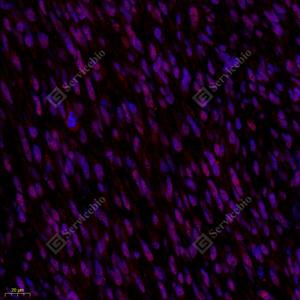

IF检测PI3 Kinase p110 beta蛋白(货号 GB112375)(红色). 样品: 人肾癌, 4%多聚甲醛 (货号G1101) 固定12-24小时. 抗原修复: Tris-EDTA抗原修复液(pH 9.0) (G1203), 98℃, 20分钟. 封闭: 3% BSA(货号GC305010)的PBS溶液, 室温孵育30分钟. —抗: 1: 650稀释, 4℃ 孵育过夜. 二抗: Cy3标记山羊抗兔IgG (H+L) (货号GB21303), 1: 300稀释, 室温孵育1小时. |